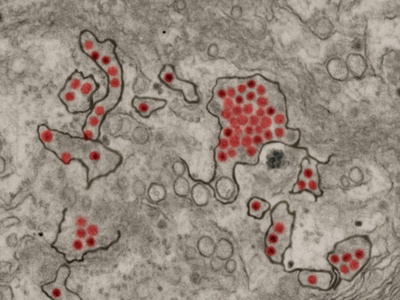

COVID-19

COVID-19 is caused by SARS-CoV-2, commonly producing fever, cough, fatigue and loss of smell; severe cases cause pneumonia and long-term symptoms. Global since 2019; spreads by respiratory routes. Vaccines and masks reduce risk; treatments and antivirals available for high-risk patients.